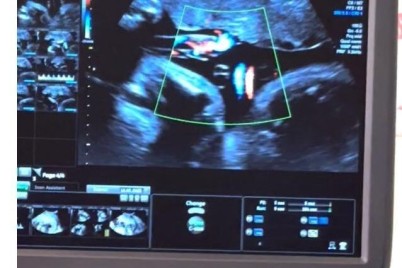

ذكر د. ماجد فادن استشاري طب الأجنة والحمل عالي الخطورة وجراحات الأجنة التداخلية بمستشفى النساء التخصصي في مدينة الملك...